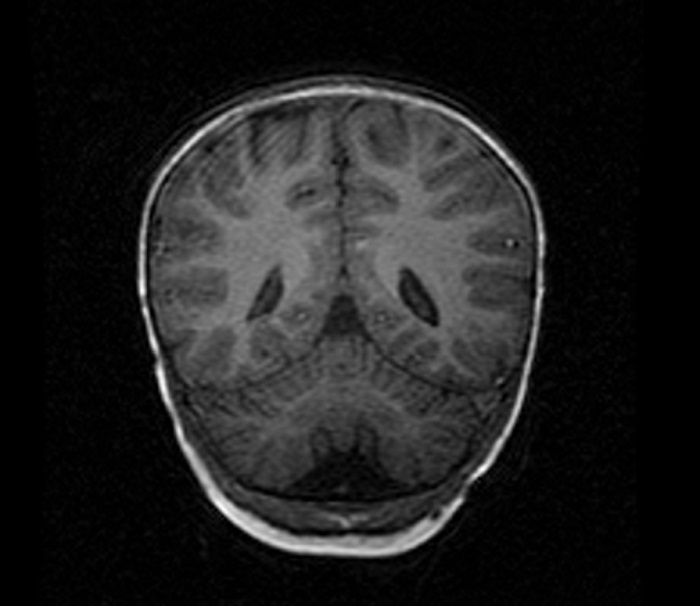

Durante el ingreso, se amplió estudio inicial solicitando electroencefalograma (normal) y estudio metabólico (incluyendo perfil de sialotransferrinas). En espera de los resultados, presenta un nuevo episodio de ataxia y movimientos oculares anormales a los 18 meses, de nuevo en contexto de proceso intercurrente, solicitando en esta ocasión estudio de neurotransmisores y lactato en LCR, con resultado normal y RM cerebral de control, con hallazgo en esta ocasión de leve atrofia cerebelosa no presente en estudio anterior. Con respecto al estudio metabólico, el perfil de sialotransferrinas estaba alterado, presentando un patrón compatible con defecto de la glicosilación tipo 1. Se solicitó estudio genético molecular del gen PMM2 con resultado patológico.